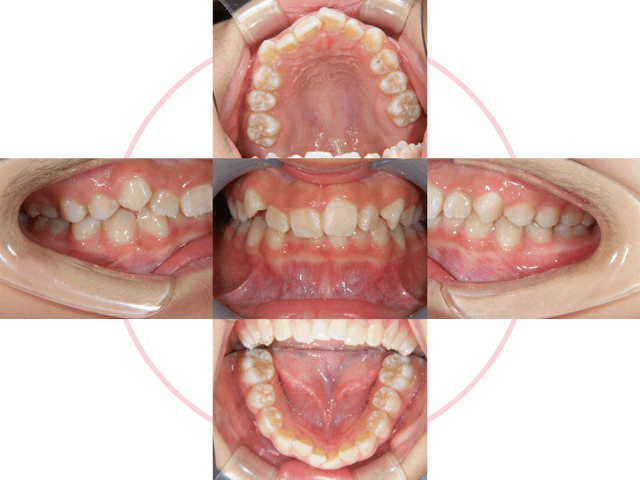

治療前

特に前歯が噛んでいない状態と八重歯は奥歯に負担がかかり、むし歯や歯周病が進行しやすい噛み合わせです。

Case 01

下の前歯が、先天的に1本少ない患者さんです。上下の歯の本数が違うために、右上犬歯が八重歯になっています。